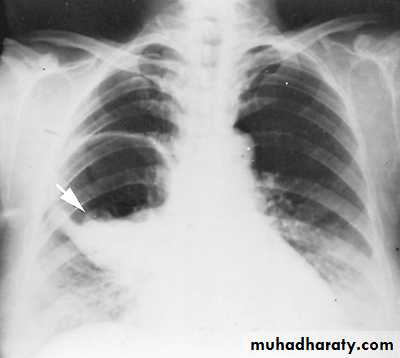

X-ray hemothorax

X-ray pneumohemothorax